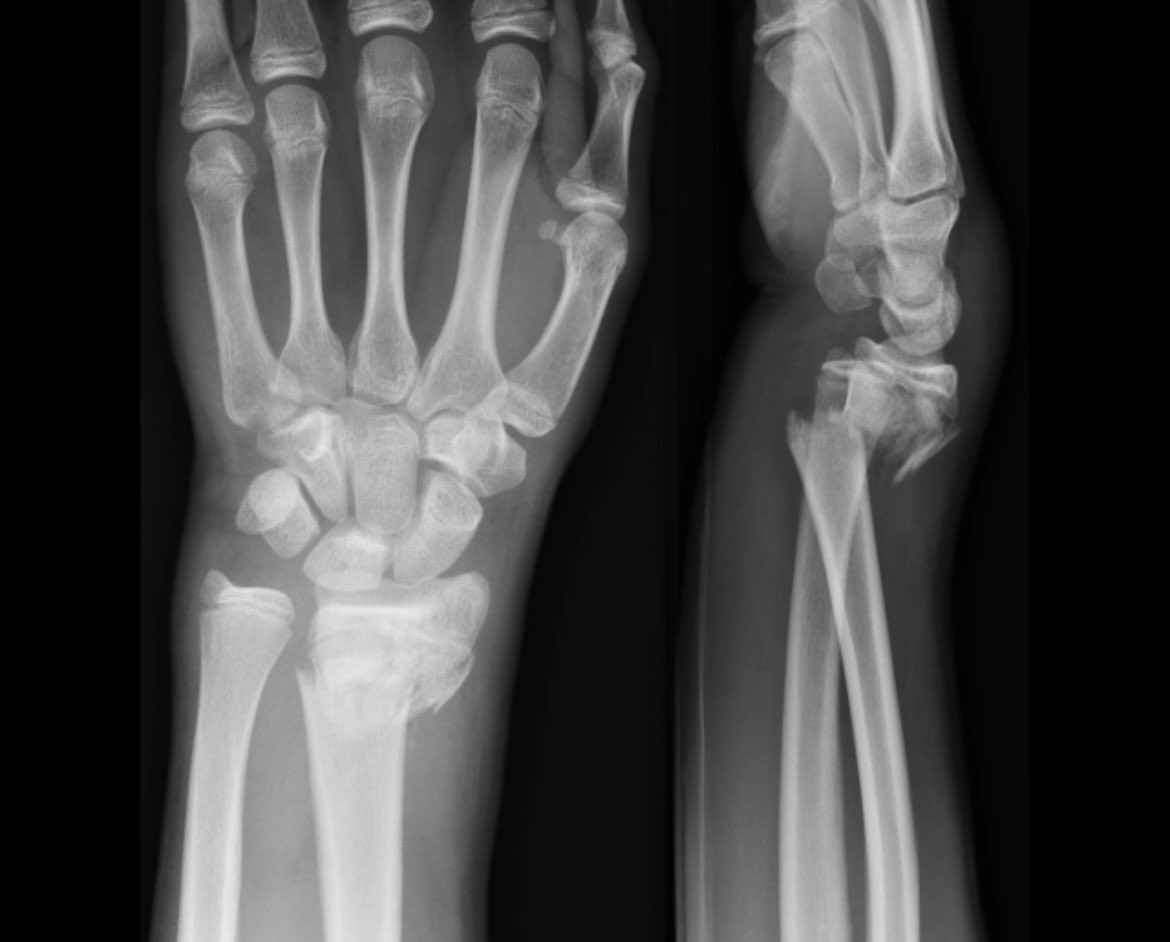

1) A 🧵 looking at EPL ruptures following distal radius fractures (DRF).

2) DRF’s are the 2nd most common # after the hip & is the most within the upper limb. This is often a Colles which occurs secondary to a FOOSH with the forearm supinated, resulting in dorsal displacement of the radius (Corsino et al., 2022).

3) EPL rupture is fortunately rare, accounting for <1% of complications post-DRF. They appear to frequently occur around 4-8/52 after the fracture & are more common in older patients as opposed to paeds (Song et al., 2013).